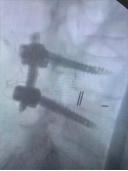

7. 复杂脊柱骨折内固定技术

随着区域内社会经济开发,复杂严重脊柱脊髓损伤病例增加,如何良好的手术治疗解除脊髓压迫、重建脊柱稳定性,使患者创伤最小、收益最大是促进患者康复至关重要的一环。我院已熟练开展各类脊柱损伤修复重建技术,每年完成复杂脊柱骨折手术处于区域领先水平。